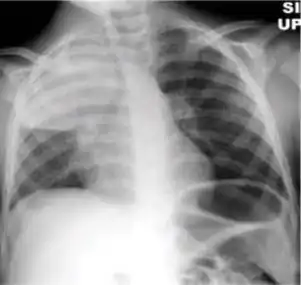

5. Hilar or mediastinal lymphadenopathy (bihilar lymphadenopathy) - Enlargement of lymph nodes in one or both hila or within the mediastinum, with or without associated atelectasis or consolidation.

Chest x-ray showing bilateral hilar adenopathy of primary pulmonary TB